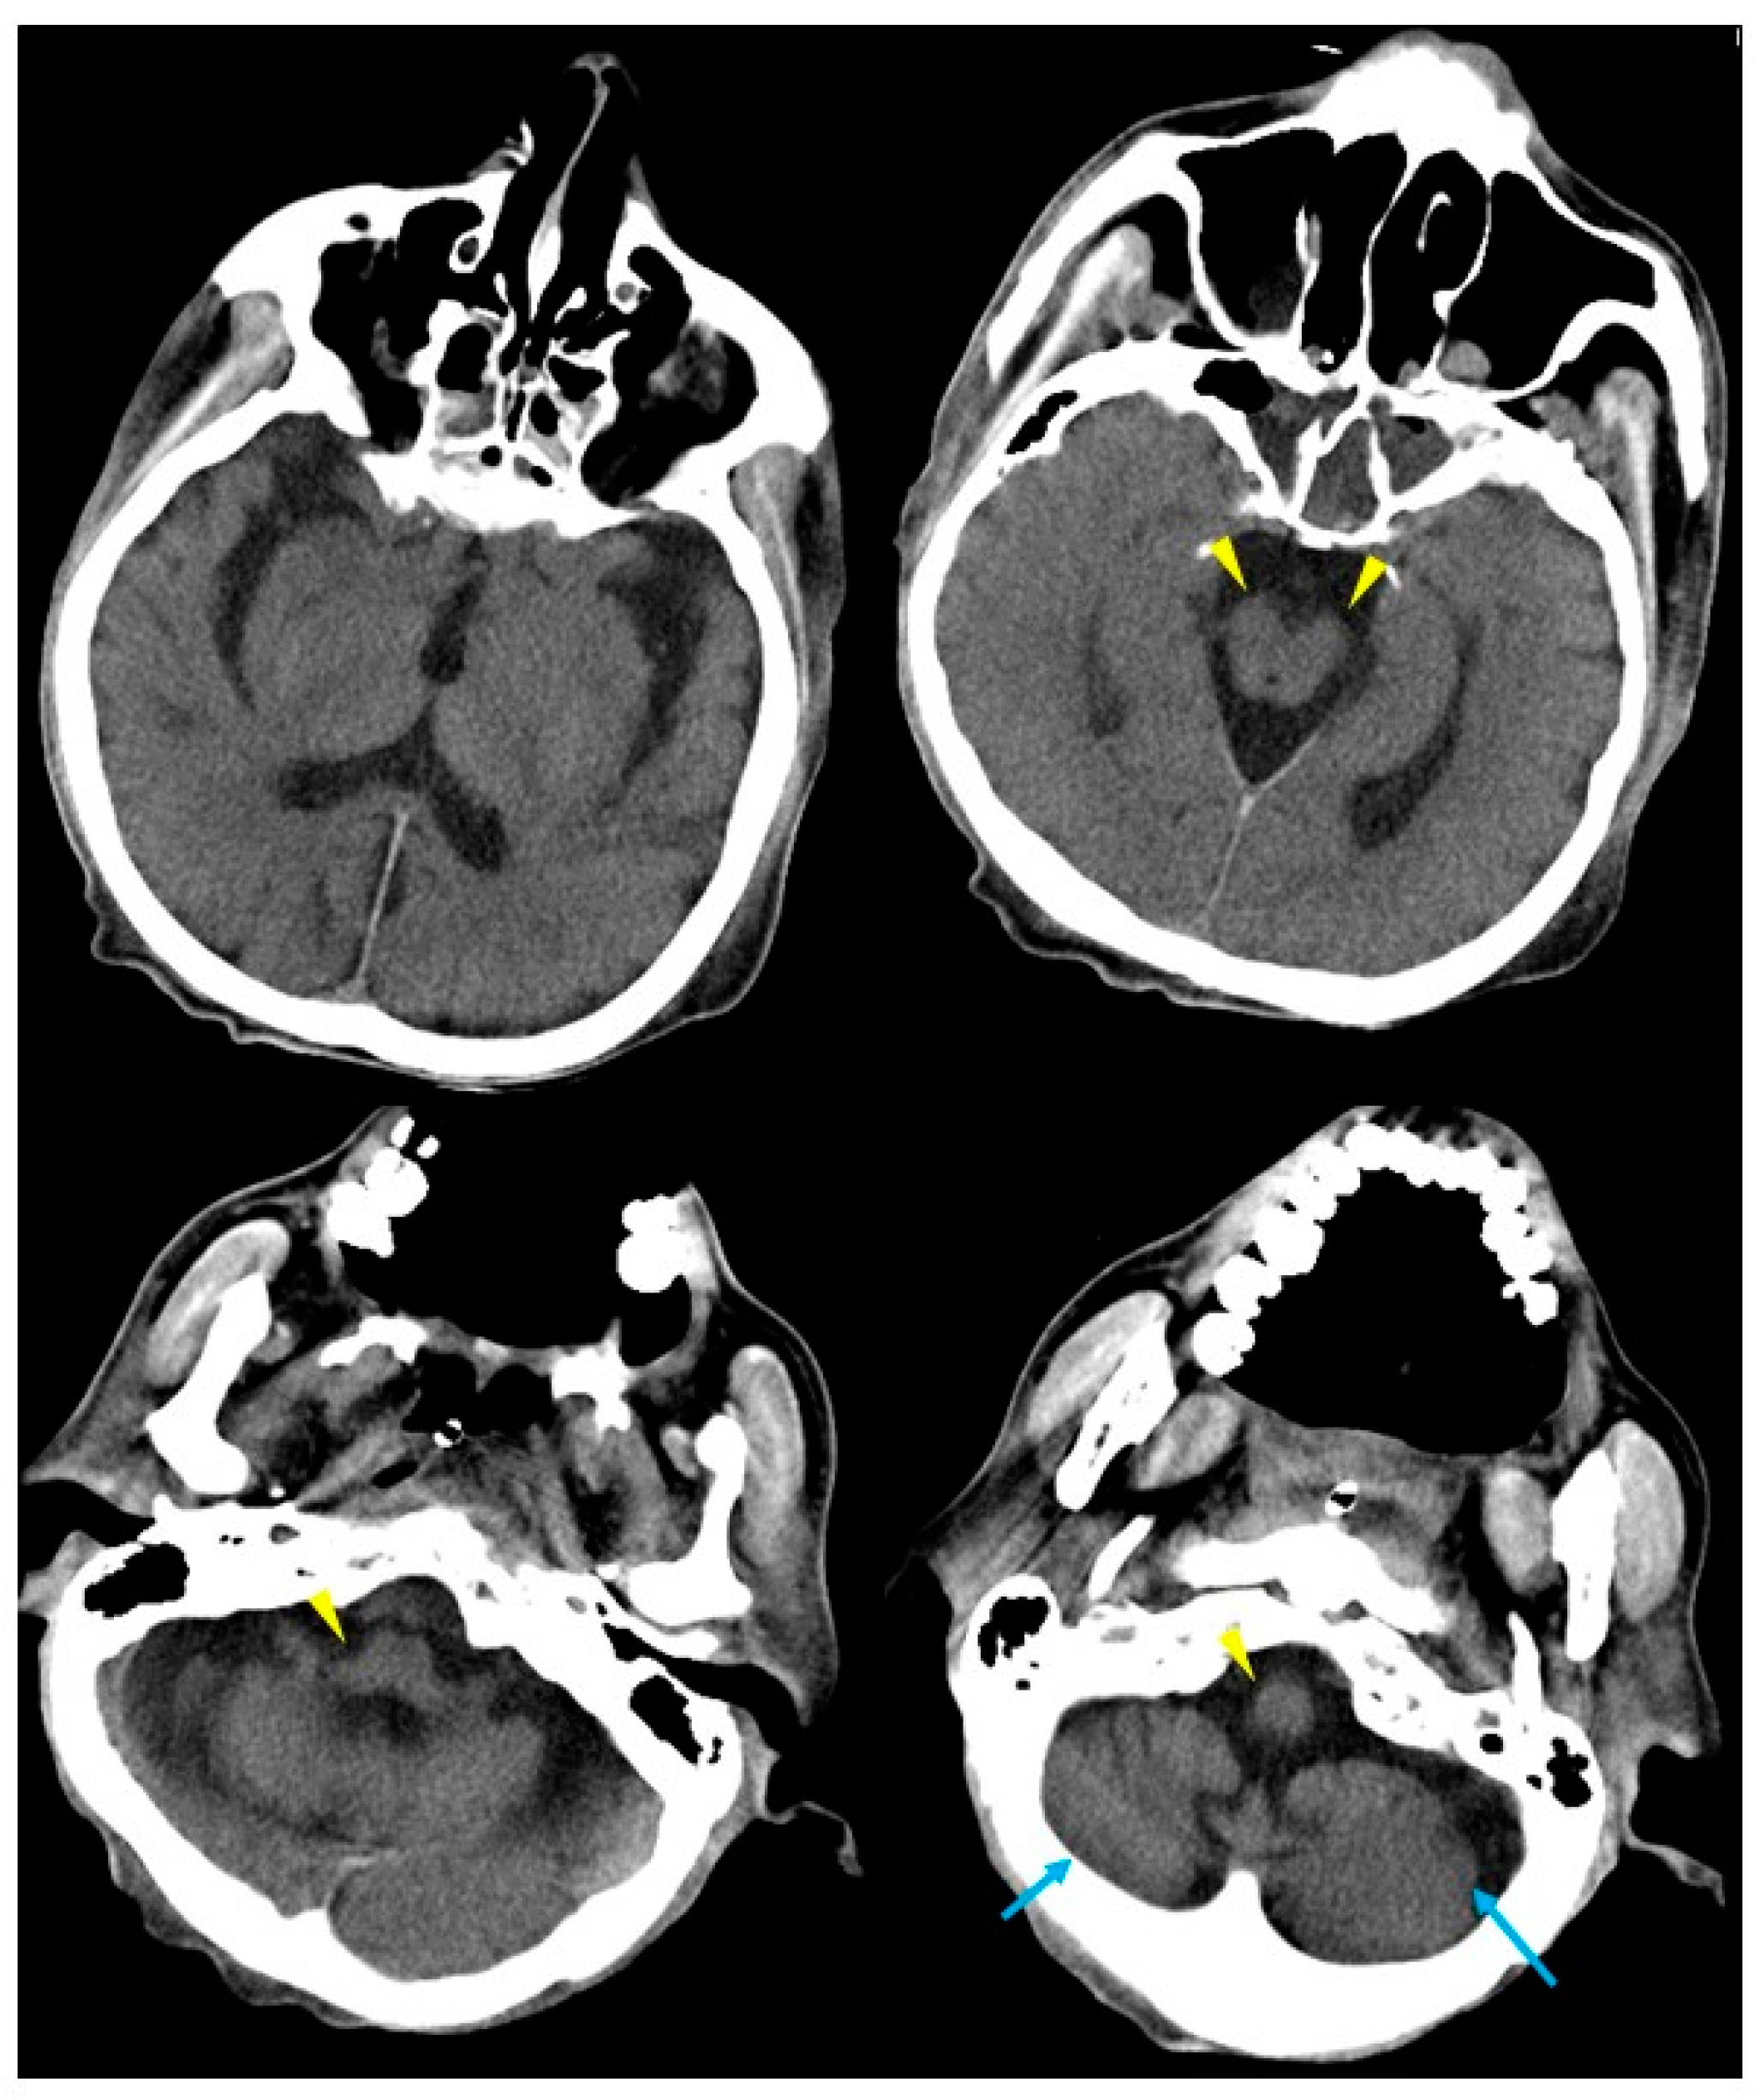

2. Case Presentation